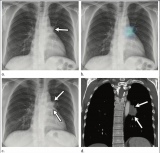

现在X射线医疗影像设备已成为医疗服务的基础设施,其中平板探测器属于核心关键部件,直接关系到医疗影像设备的性能和质量,其核心底层技术主要涉及传感器芯片及信号处理等多方面。 2021-03-03 放射诊疗辐射成像

X射线成像领域的重大突破 苏州学者再发顶级期刊

继2月初该研究院卞劲松团队在《Science》子刊发表帕金森病治疗新发现后,最近,该院首席研究员刘小钢团队再次在国际顶级学术期刊《Nature》上发表X射线成像领域的重大突破。 2021-03-03 辐射成像